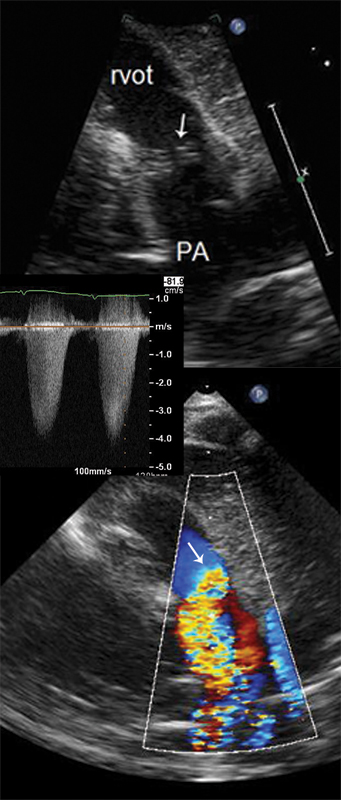

فحوصات تشخيصية لبعض امراض القلب والشرايين التاجية